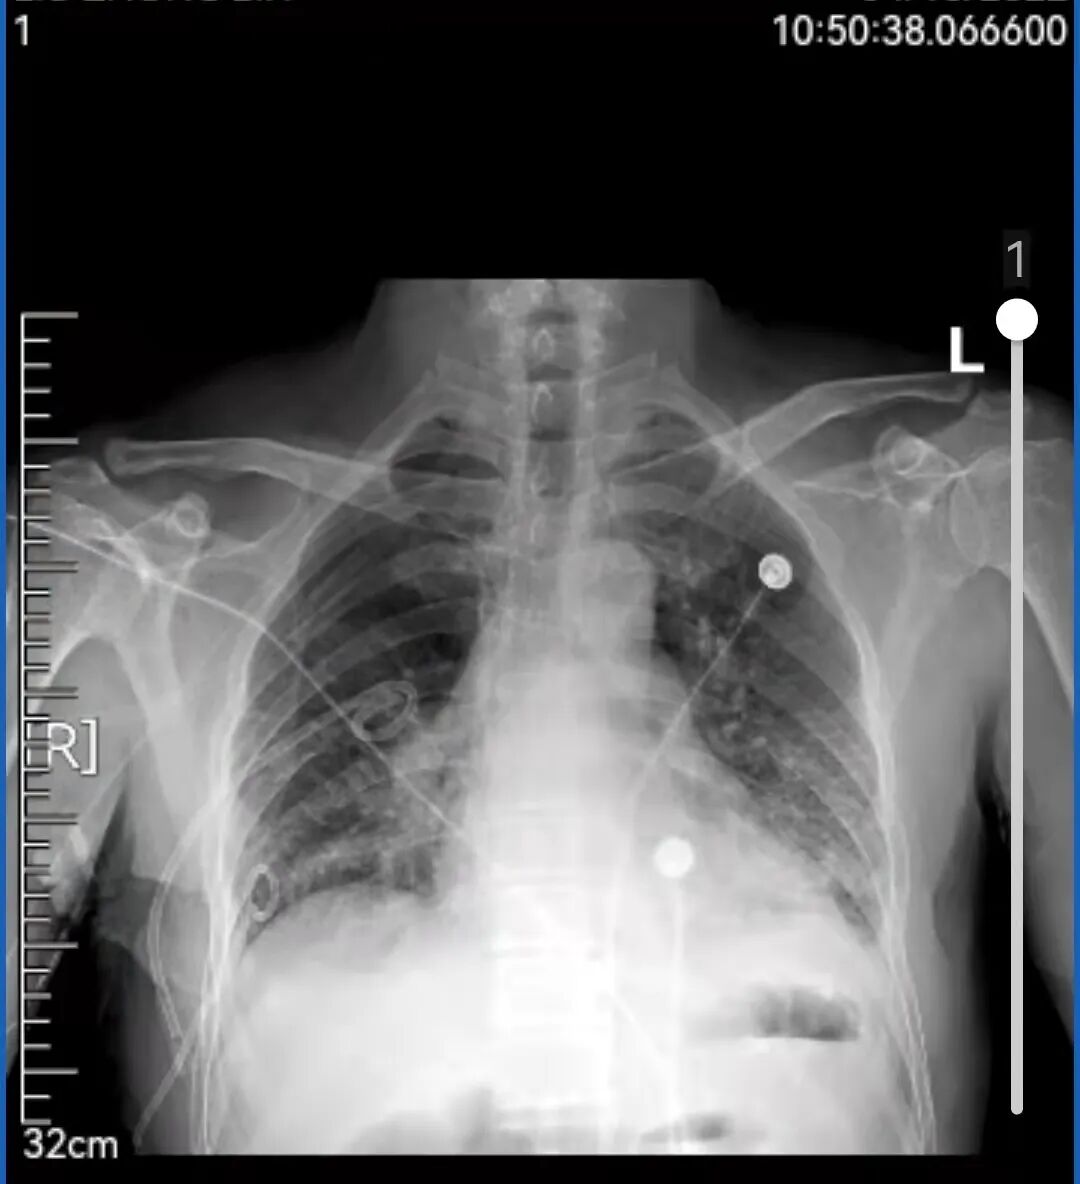

0岁的刘先生平时身体一直不错,登山、跳绳、骑行样样行。像他这样的年龄血压、血糖等都在正常值范围内,身体素质甚至比年轻的小伙子还好。因为没有这疼那痒,五年内从没体检过。 上个月不小心被车撞了一下,到辽宁省肿瘤医院拍了个肺部CT进行检查,这一查不要紧,除了受损的两根肋骨外,“眼尖”的医生居然在CT片子上发现了一个“恶魔”,在其右肺上叶有一个接近5cm的肺结节。 影像资料 辽宁省肿瘤医院胸外科团队接诊后,耐心地询问刘先生,可刘先生既没有吸烟史也没有癌症家庭史,每天在公园暴走上万步的刘先生,会跟“肺癌”这两个字联系在一起吗? 影像资料 为了不给刘先生及其家属带来恐慌,又不能耽误病情,胸外科团队请来了专家为其进行多学科会诊(MDT),“我们不敢冒然行事,也不敢错过手术最佳时机,因为从这个肺结节的形态上来看,如果是肺癌的话,行手术根治术+淋巴清扫,预后效果应该还是不错的”。 手术中 经多学科会诊,专家们建议为刘先生行CT引导下穿刺,以进一步明确病理。病理结果出来后,跟专家们的预想差不多,病理提示“肺腺癌”,胸外科为刘先生做了单孔胸腔镜下的肺癌根治术+淋巴清扫术。术后刘先生恢复很快,5天就出院了。因为是早期肺癌,发现得早,及时手术切,刘先生并不需要化疗、放疗,刘先生悬着的心终于放下了,说道“要不是这场车祸,不然还不知道什么时候会发现,也有可能发现时就是晚期了呢” 早期肺癌治愈率高,定期体检是关键。祸兮福之所倚,福兮祸之所伏。短短一个月内,刘先生经历了“车祸——肺结节——肺癌——手术根治”的跌宕人生。像刘先生这样因为外伤检查住院而意外发现早期肺癌的患者,医院也收治了不少。因为早期肺癌相当隐匿,几乎没有什么症状。如果缺乏定期体检,不做胸部CT,早期肺癌是难以发现的。而等患者发现时就已经到了中晚期了,不仅治疗复杂费钱,效果还不好。 辽宁省肿瘤医院胸外科专家介绍,早期肺癌治愈率较高,其中原位癌及微浸润腺癌治愈率可达90%--100%,且不需要放疗、化疗,治疗费用低,生存质量也高。而中晚期肺癌的五年生存率只有20%--50%。所以,定期体检非常重要。但值得注意的是,大部分肺结节是良性的,只有30%--40%的肺结节可能是早期肺癌。即便是早期肺癌,通过微创手术切除治疗效果也较好。